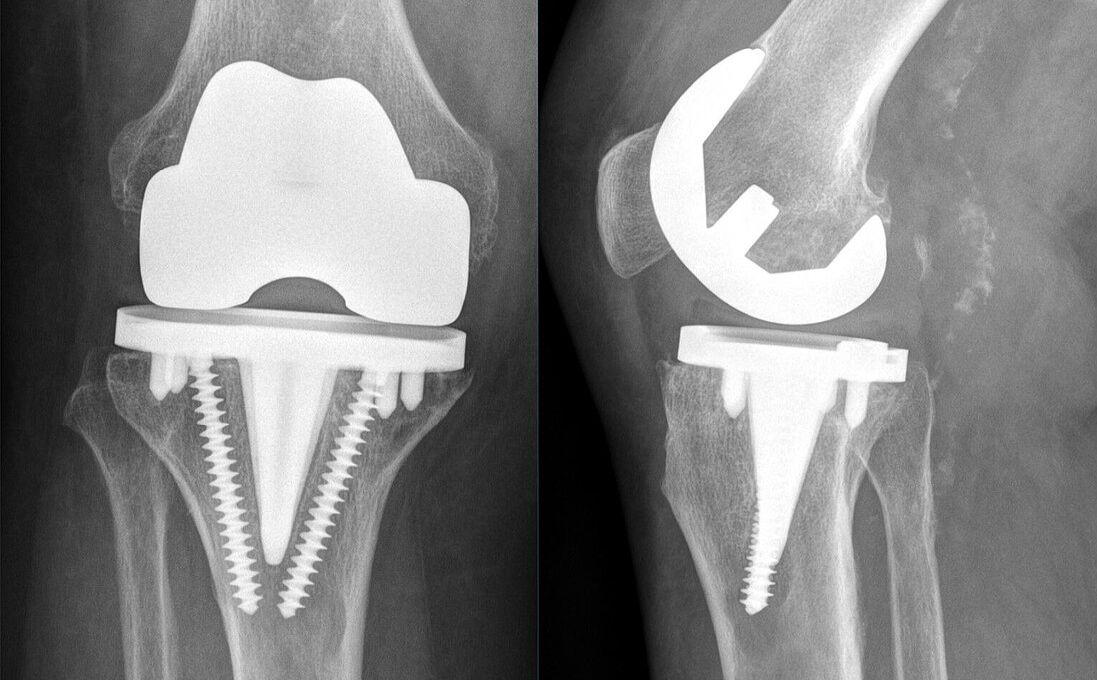

Deutlicher Anstieg bei Knieprothesen

Endoprothesenregister meldet Rekordzahlen in der Endoprothetik.

Foto: Hellerhoff • Lizenz: CC-BY •

Die Zahl der eingesetzten Knie- und Hüftgelenke steigt weiter rasant. Laut dem aktuellen Jahresbericht des Endoprothesenregisters Deutschland (EPRD) wurden im letzten Jahr 410.333 Eingriffe gezählt – so viele wie nie zuvor. Besonders deutlich zeigt sich der Trend am Knie: 173.252 Erstimplantationen bedeuten einen Zuwachs von über 36.000 Operationen seit 2022. Auffällig hierbei ist: Kniepatientinnen und -patienten sind im Schnitt jünger und haben einen rund drei Punkte höheren BMI als Menschen mit Hüftprothesen. Vor allem in den jüngeren Altersgruppen nimmt das Gewicht als Risikofaktor weiter zu.